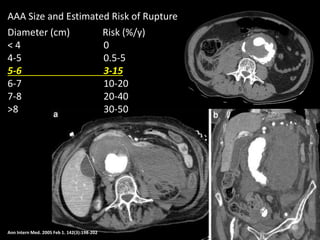

Ann Intern Med. 2005 Feb 1. 142(3):198-202

AAA Size and Estimated Risk of Rupture

Diameter (cm) Risk (%/y)

< 4 0

4-5 0.5-5

5-6 3-15

6-7 10-20

7-8 20-40

>8 30-50